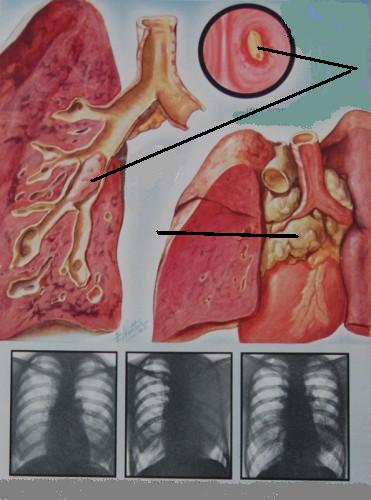

Прогрессирование

деструктивного

процесса

с отсутствием признаков формирования пиогенной капсулы (а);

сообщение полости гнойника с одним из бронхов (б).